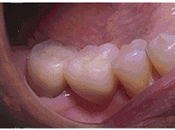

インプラント術後

右下奥の歯のないところにインプラントを埋め込みました。

これまで反対側の歯や前歯でしか食事ができずイライラしていたようですが、インプラントが入って以来、おいしく食事ができるようになったようです。